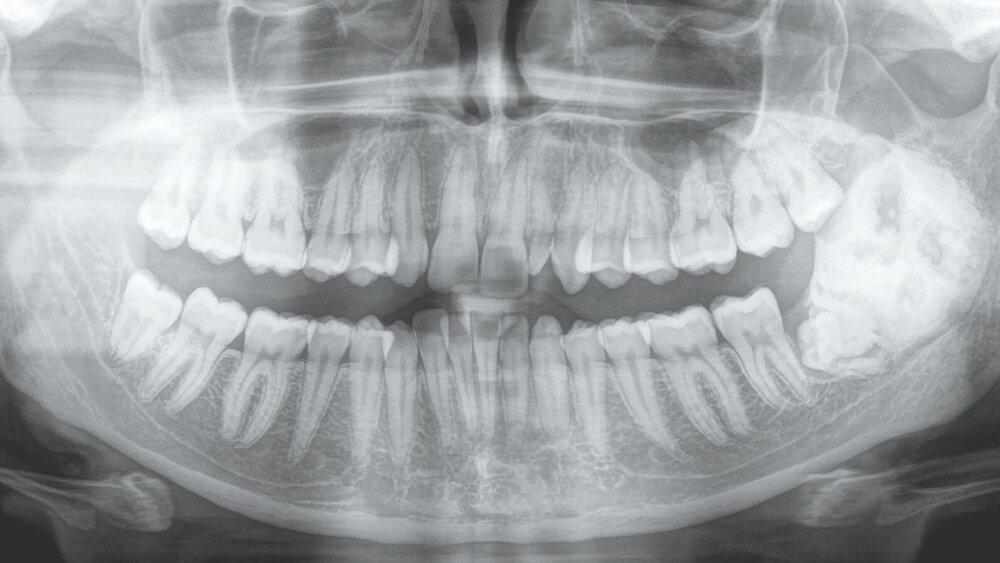

Eine 23-jährige Patientin stellte sich bei einem zunehmenden Druckgefühl im Kieferwinkel links in unserem Klinikum vor. Klinisch imponierten intraoral lediglich Verbreiterungen der Mandibula in regio 38 sowie des Ramus ascendens links. Der N. alveolaris inf. zeigte eine regelrechte Funktion. Eine faziale Asymmetrie bestand nicht. Es erfolgte die Anfertigung eines Orthopantomogramms (Abbildung 1), das eine ausgedehnte Verschattung im Kieferwinkel links zeigte. Da es keine älteren Röntgenaufnahmen dieser Region gab, konnten keine Aussagen über den Wachstumszeitraum der Raumforderung getroffen werden.

Zur weiteren Diagnostik wurde eine Computertomografie angefertigt und zur histologischen Sicherung eine Probebiopsie in regio 38 in Lokalanästhesie durchgeführt. Die histopathologische Begutachtung des mit dem Trepanbohrer entnommenen Knochenzylinders zeigt, dass ein komplexes Odontom vorlag.